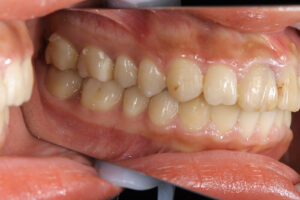

ワイヤー矯正で全体の歯が噛んでいる